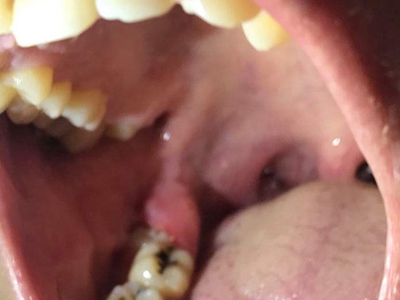

智齿冠周炎右下方的牙龈最内侧红肿图

智齿冠周炎患者右下方的牙龈最内侧有红肿,红肿处有一小创口,可见其内的牙齿,牙齿未完整露出,小创口边缘微微发白,患者自觉有明显疼痛。